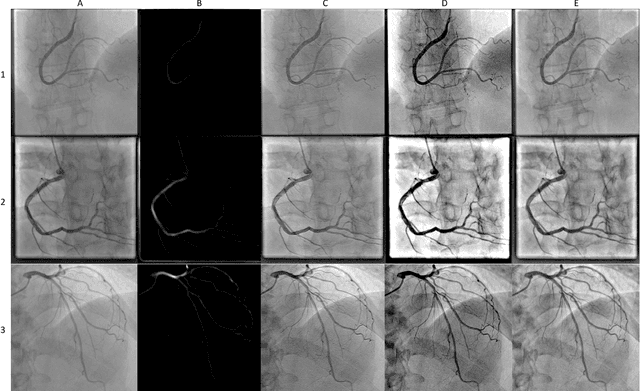

Abstract:Coronary Heart Disease (CHD) is a leading cause of death in the modern world. The development of modern analytical tools for diagnostics and treatment of CHD is receiving substantial attention from the scientific community. Deep learning-based algorithms, such as segmentation networks and detectors, play an important role in assisting medical professionals by providing timely analysis of a patient's angiograms. This paper focuses on X-Ray Coronary Angiography (XCA), which is considered to be a "gold standard" in the diagnosis and treatment of CHD. First, we describe publicly available datasets of XCA images. Then, classical and modern techniques of image preprocessing are reviewed. In addition, common frame selection techniques are discussed, which are an important factor of input quality and thus model performance. In the following two chapters we discuss modern vessel segmentation and stenosis detection networks and, finally, open problems and current limitations of the current state-of-the-art.